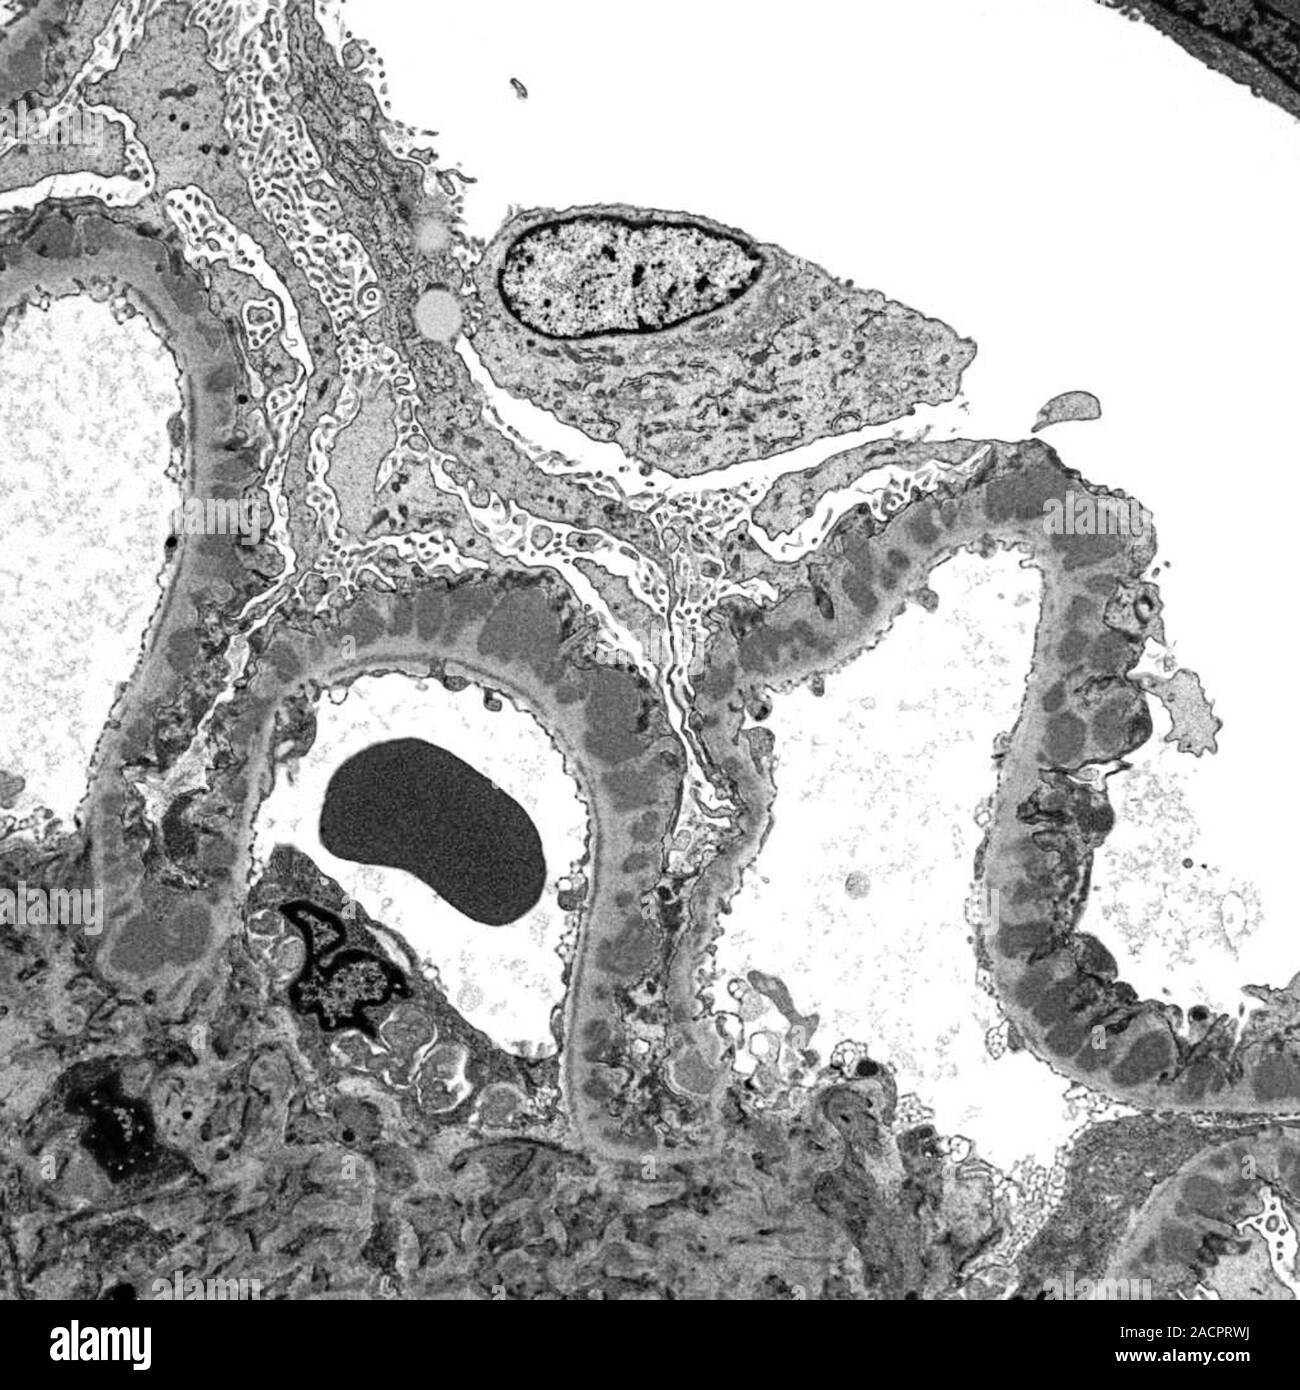

Glomerulus. Transmission electron micrograph (TEM) of a section through Transmission Electron Microscopy Glomerulus Transmission em (tem), commonly used in diagnosis and research, focuses high energy (100 kv and higher) electrons with lenses to form images in a way similar to. Diabetic nephropathy (dn), the single strongest predictor of mortality in patients with type 2 diabetes, is characterized by initial. We have used a new approach involving serial section electron microscopy to fully reconstruct. Transmission Electron Microscopy Glomerulus.